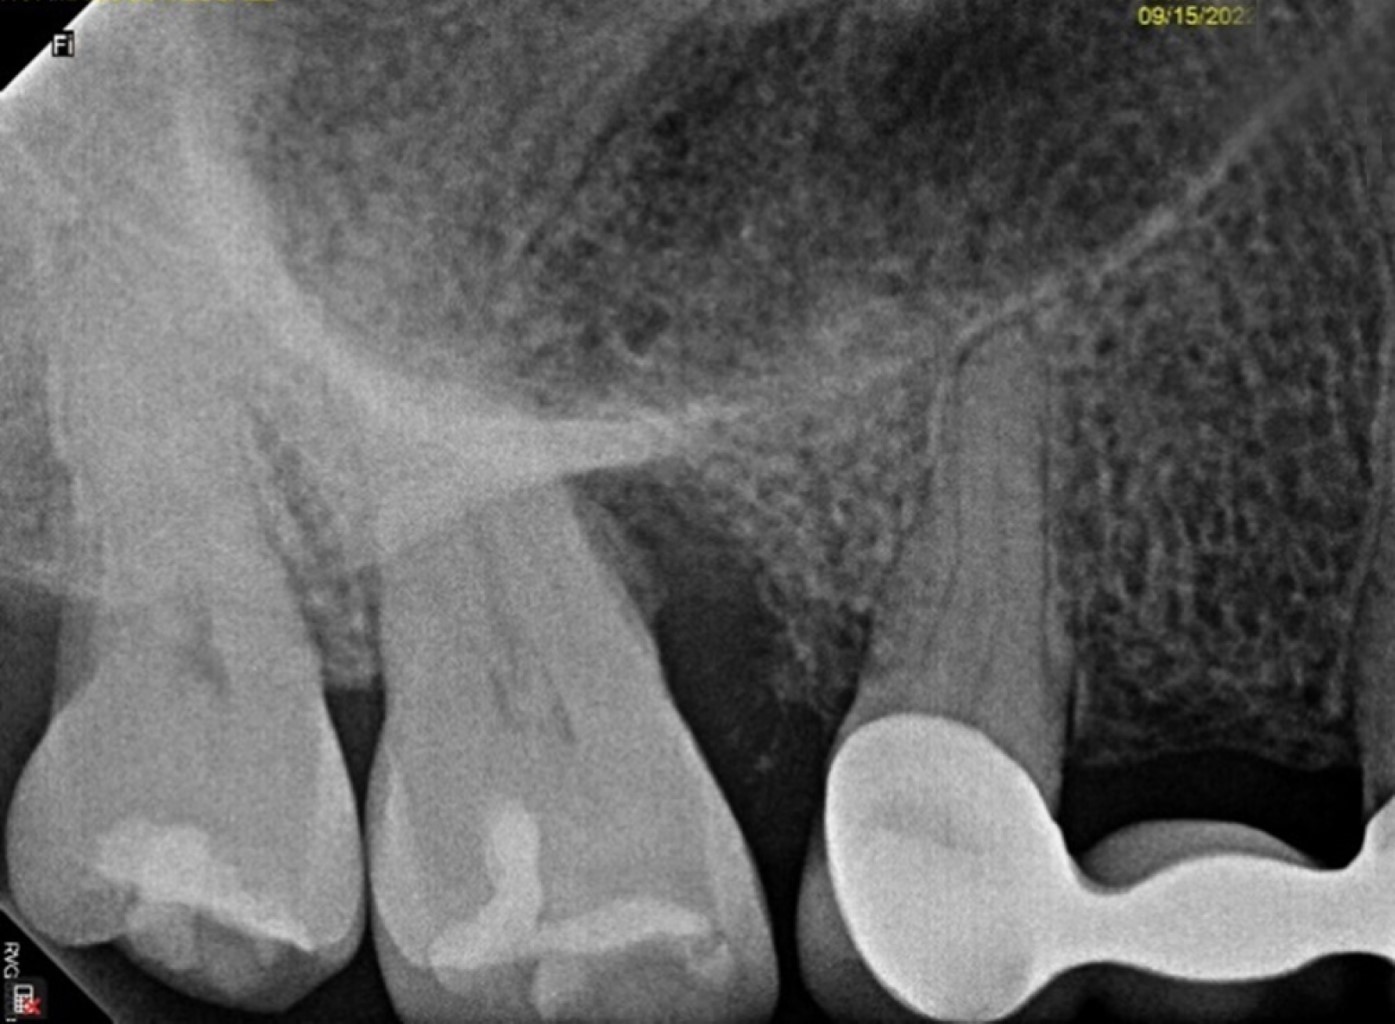

Se presenta, en la Especialidad en Periodoncia de la Universidad Autónoma de Baja California (UABC) campus Mexicali, un paciente femenino de 60 años, ASA I, sin antecedentes patológicos, cuyo motivo de consulta es "tengo una bolsa periodontal desde los ocho años". Se realizó una evaluación extraoral en la que se detectó hipertrofia bilateral del músculo masetero, de manera intraoral se observó un fenotipo delgado, presencia de restauraciones desajustadas, desgaste por bruxismo en bordes incisales y cúspides. En el análisis clínico-radiográfico se obtuvo una profundidad de sondaje de 12 mm, efecto intraóseo de una pared según la clasificación de Goldman & Cohen (Figura 7) por vestibular del segundo molar superior derecho, movilidad grado II, con presencia de sangrado, sin sensibilidad. Radiográficamente se observó una zona radiolúcida adyacente a la raíz mesial del segundo molar superior derecho sin presencia de lesión periapical (Figura 8) y, por lo tanto, se estableció el diagnóstico según la "Clasificación de Condiciones y Enfermedades Periodontales y Periimplantarias 2017" como: salud gingival y periodontal en un periodonto reducido, paciente no periodontal, asociado a un trauma oclusal primario;11 y como factor de riesgo se tiene el antecedente de la pérdida prematura del primer molar superior derecho y la mesialización del segundo molar superior derecho.

Figura 7

Figura 8